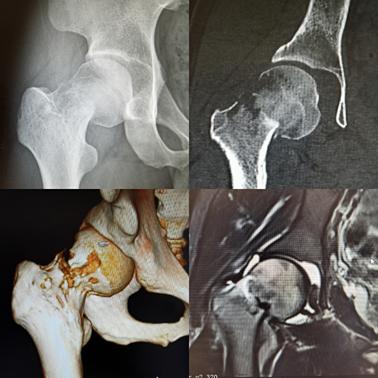

25岁的一位青少年,长期髋部疼痛

起初未影响正常生活,遂未予重视。

后来在一次登山时突发不适,腿痛难忍

被朋友搀扶下山,而后来到罗医集团罗湖中医院

(上海中医药大学深圳医院)脊柱骨科就诊,

经诊断患者为右髋部骨折。

对于一个25岁的青少年而言,在没有受任何外伤的情况下发生骨折,极有可能是病理性骨折。为此,医护人员为他进一步完善检查,诊断结果提示患者右髋部病理性骨折,骨质破坏(性质待查),如不能顺利康复,患者只能暂时卧病在床。

经术中探查发现,患者右侧股骨出现颈旁类肿瘤组织,医护人员遂为患者行术中冰冻病检,检查提示小圆细胞瘤,淋巴、血液来源可能。

由于患者的病灶局限于股骨颈及股骨近端,专家决定为患者实施双动头人工股骨头肿瘤假体置换,而非全髋关节置换,这样做的意义是保留髋臼的软骨组织,因为软骨是骨肿瘤突破的天然屏障,保留软骨以阻断肿瘤细胞向髋臼侵犯。

手术的过程中,专家提取大量骨肿瘤组织,再次进行病理活检,检查结果提示为非霍奇金淋巴瘤、弥漫性大B细胞淋巴瘤。手术治疗后,医护人员对患者进行基因筛查,寻找靶向药物治疗,后期进一步综合治疗。